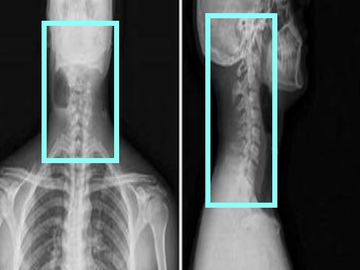

Helical Supine

2.5x2.0 GE bone/2.0x2.0 Siemens bone 2000W 500L

2.5x2.0 Ge standard / 2.0x2.0 Siemens standard 400W 40L

0.625x0.625 GE bone and standard / 0.75x0.7 Siemens bone and standard

Reformats:

coronal 1.25x1mm GE bone and std

coronal 1.5x1.0 Siemens bone and std

sagittal 1.25x1.0 GE bone and std

sagittal 1.5x1.0 Siemens bone and std

angled reformats through each disc space 1mm 15 FOV standard algorithm (if ordered)

VRT rotate and tumble every 10 degrees (If ordered or hardware is present)